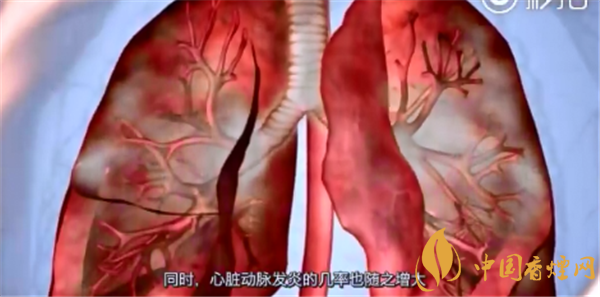

现代肿瘤学认为,癌症是基因突变的产物,癌症发生是突变逐渐积累的过程。最新的研究结果第一次系统性地对比了吸烟和不吸烟肺癌的DNA,发现了惊人的结论:虽然肺癌表面看起来很相似,但吸烟者肺癌中基因突变的数目是不吸烟者中的10倍还多!

吸烟与肺癌的关系正常细胞基因组如果是整整齐齐排队的解放军的话,那么不吸烟肺癌细胞基因则像是拥挤的火车站的人流一样无序;而吸烟患者肺癌细胞可能变成了爆炸后的现场,一片狼藉。

第三,基因突变较多的细胞更容易获得生长上的优势。如果一个细胞存在的突变较多,那么这个细胞更容易增殖,也就是比别的细胞生长更快,繁殖更多,以至于形成优势细胞,所以这种存在多个突变的癌细胞易形成肿瘤。

最经典的是1951年英国医学协会对英国医生进行的吸烟习惯的研究,此研究对这些医生进行观察了50年,发现吸烟与肺癌的关系:吸烟明显增加了肺癌发病率,不仅仅是肺癌,吸烟还导致了心肺疾病、慢性阻塞性肺疾病和血管疾病的发生率。男性吸烟患肺癌的机率是不吸烟者的23倍,女性是13倍。套用一句现代流行的话,吸烟者也是蛮拼的,将生死置之度外。